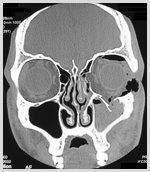

Orbital fracture

Trauma in and around the eye can cause fracture of the orbit .Surgery to repair the fracture is carried out as early as possible to prevent permanent damage..Orbital eye fracture is the repair of the fracture that involves orbital bones around the eye. In such fractures, the rim and the bones linking the inside of the orbit is operated. Medpore sheets are used to support the fracture site. Deformities of the face, reduced eye movement, double vision or sinking of the eye into the orbit can be the consequences of such fractures, which are treated through repair.